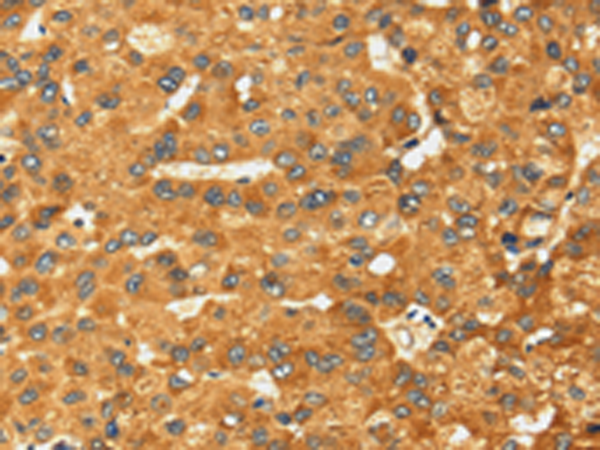

分类: 科研抗体货号: P08713别名: GRAIL应用: IHC反应种属: Human, Mouse